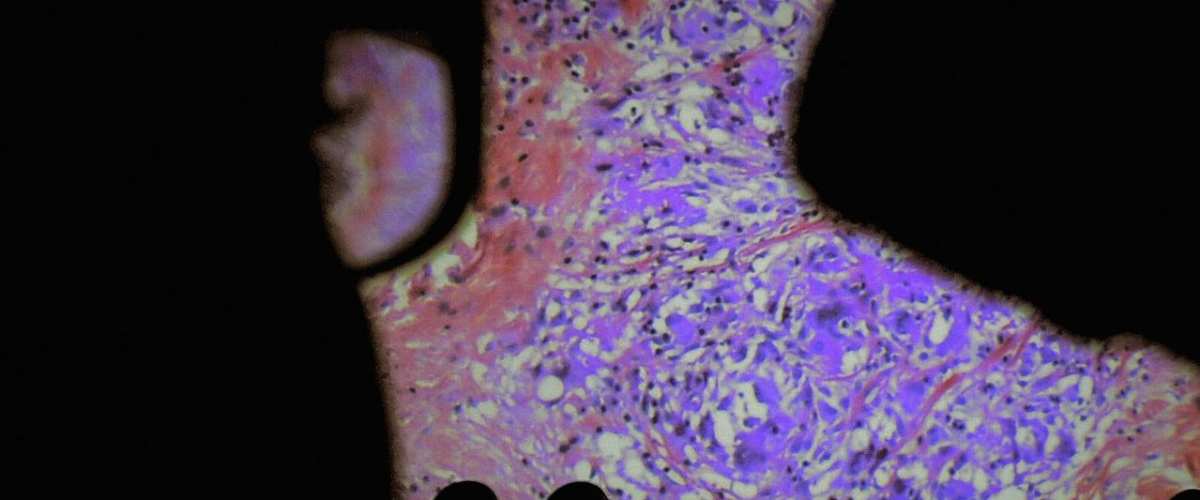

Five centuries ago, anatomist André Vésale opened up the human body to science for the first time in history. Today, De Humani Corporis Fabrica opens the human body to the cinema. It reveals that human flesh is an extraordinary landscape that exists only through the gaze and attention of others. As places of care, suffering and hope, hospitals are laboratories that connect every body in the world.